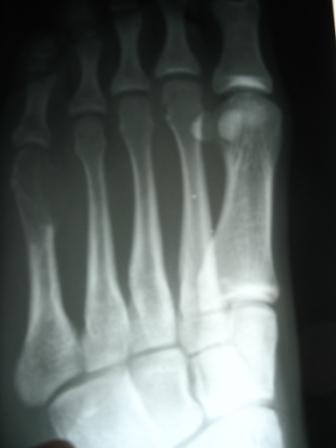

Среди методов диагностики основное значение и имеют плантография (обнаружение поперечного плоскостопия посредством отпечатков ступней) и рентгенологическое исследование (рентгенография в прямой под нагрузкой и боковой проекции). |

Определение степени деформации стоп проводится на основании рентгенографической оценки ряда параметров: угол вальгусного отклонения первого пальца (М1-Р1), угол варусного отклонения первой плюсневой кости (М1-М2), угол PASA.

I степень: отклонение I пальца кнаружи (угол M1-P1) < 25° |

| II степень: отклонение I пальца кнаружи (угол M1-P1) > 25° отклонение I плюсневой кости кнутри (угол M1-M2) < 18° угол PASA — нормальный или негативный |

III степень: отклонение I пальца кнаружи (угол M1-P1) > 35 ° |

Слева: рентген перед операцией. Кружком обозначен вывих второго пальца стопы.

Справа: рентгеновский снимок после операции, показывающий правильное положение второго пальца ноги.

Диагноз подтвержден рентгеном. Обычно головка пораженной плюсневой кости расширена и уплощена, а плюсневой сустав может быть склеротическим и нерегулярным. Рентген также полезен для исключения различных состояний, способствующих метатарзалгии.